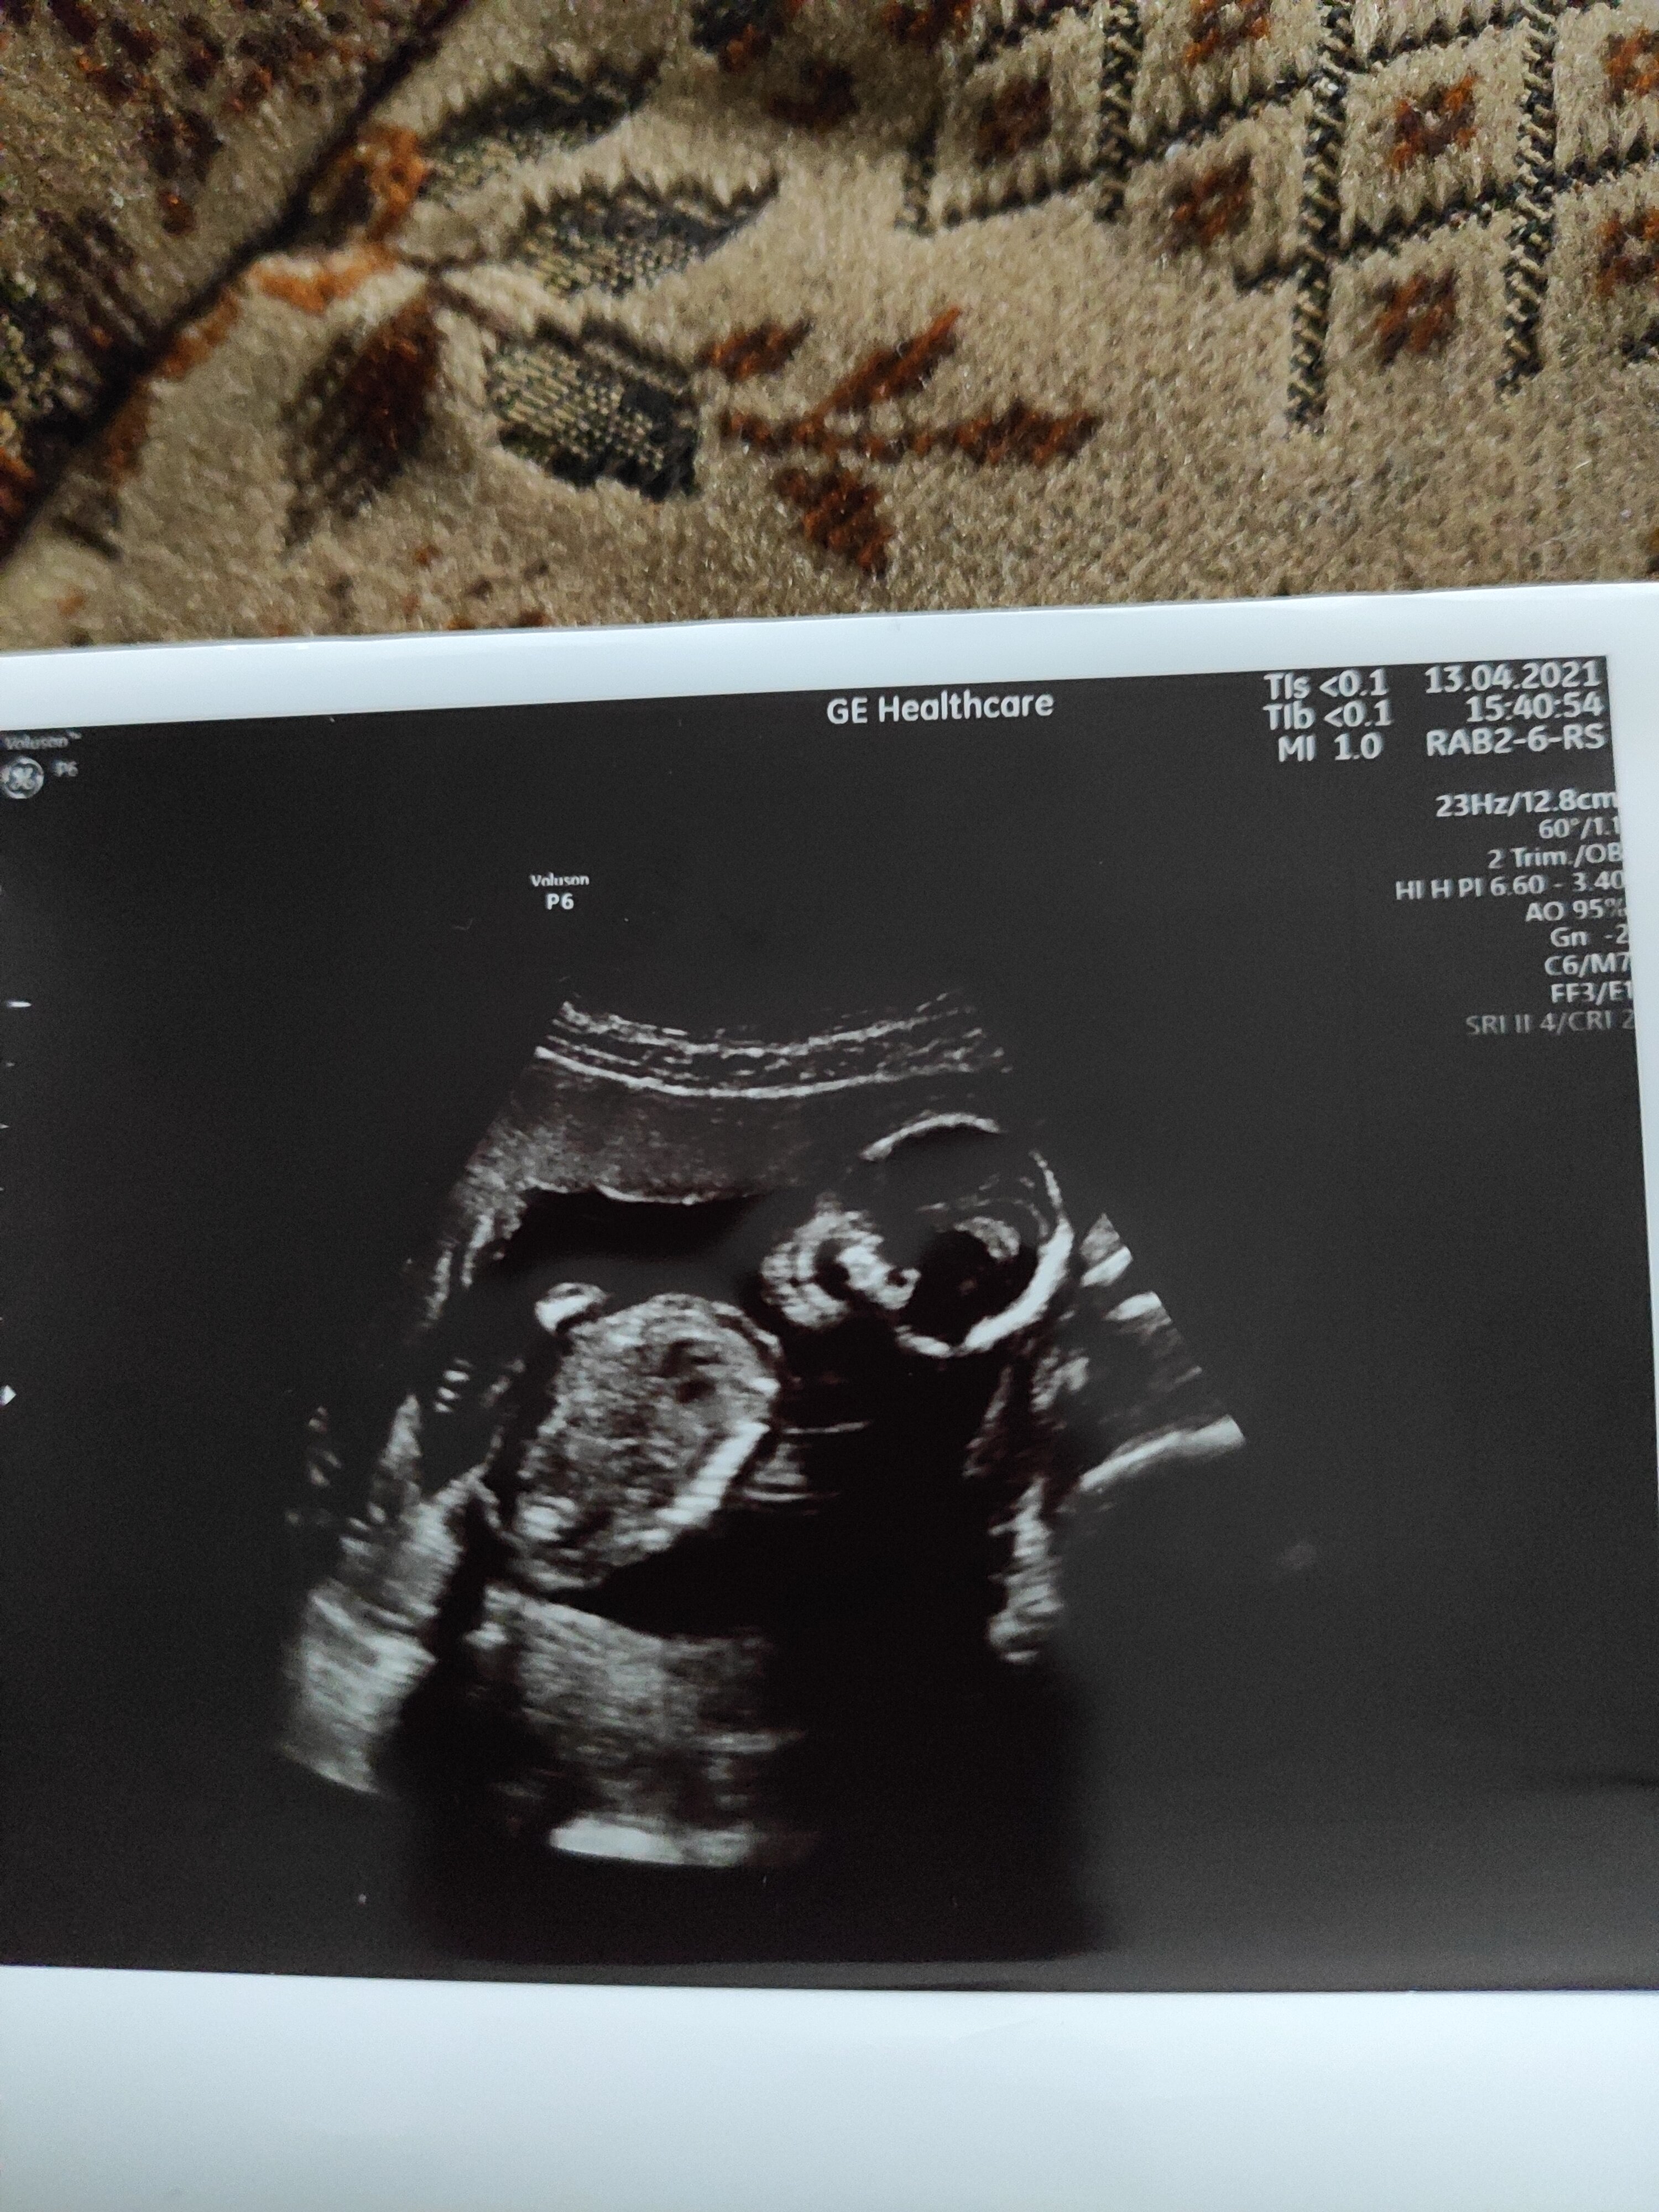

Jeśli lekarz Ci powiedział, że KONKRETNIE NA TYM zdjęciu widać płeć dziecka, to po prostu robił sobie z Ciebie jaja

No widzisz i to badanie prenatalneJeśli lekarz Ci powiedział, że KONKRETNIE NA TYM zdjęciu widać płeć dziecka, to po prostu robił sobie z Ciebie jaja![]()

Nie widać nuba. Który to tydzień ciąży? Dziecko wygląda na małe.Witam czy jest ktoś kto widzi płeć z tych zdjęć